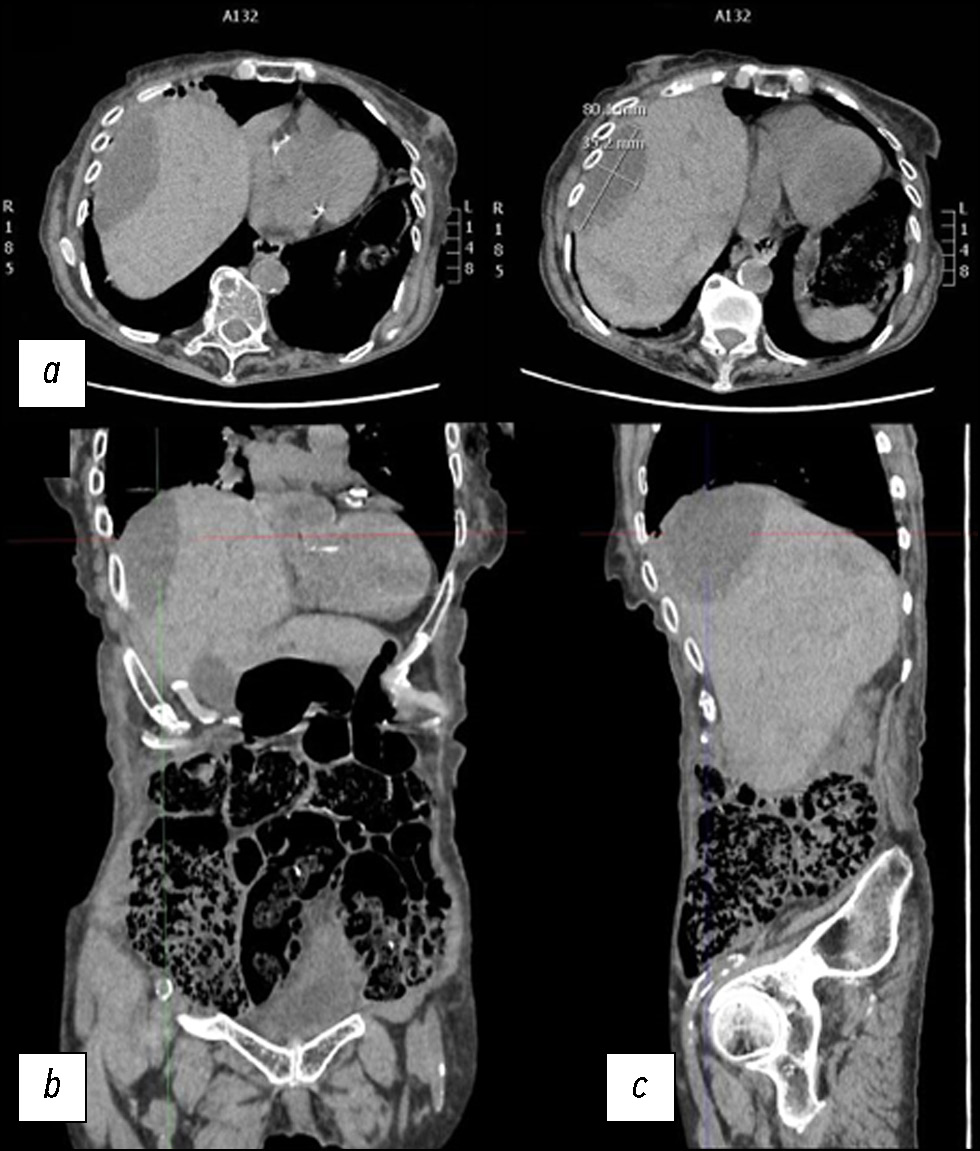

Случай спонтанного разрыва печени и роль визуализации: от компьютерной томографии до интервенционного лечения

Разрыв паренхимы печени — редкое, но потенциально смертельное состояние, которое может быть вызвано травмой, ятрогенными факторами, спонтанными причинами и так далее. В данной статье описан клинический случай, в котором представлены диагностические и терапевтические меры, применённые в ходе лечения пациентки со спонтанным разрывом паренхимы печени. Пожилая женщина поступила в отделение неотложной помощи с болью в животе диффузного характера. После клинического обследования ей была проведена компьютерная томография. По результатам первой компьютерной томографии не выявили полномасштабного разрыва паренхимы. Из-за неоднозначности данных, указывающих на то, что боль в животе могла быть вызвана почечной или желчной коликой, поставить ранний диагноз было очень проблематично. В паренхиме печени было обнаружено лишь несколько гиподенсных образований овальной формы, наполненных жидкостью повышенной плотности. Однако боль сохранялась в течение нескольких дней, и ввиду ухудшения состояния пациентки были проведены дополнительные рентгенологические исследования, по результатам которых выявили разрыв паренхимы печени. Это потребовало в дальнейшем применения метода артериографии, а также длительного пребывания в стационаре до клинического разрешения.